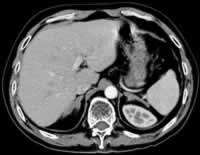

患者,男性,51岁。因反复上腹不适8年,发现双侧肾上腺占位性病变24天,于2003年10月入院。

患者于8年前无明显诱因出现上腹部不适,饱胀、嗳气,在当地医院做胃镜示“慢性浅表性胃炎”,对症治疗2~3个月后症状缓解而自行停止治疗;此后偶有上腹部不适,但皆未在意。入院前24天病人又出现上腹部饱胀不适,且较以往加重,在当地医院做腹部CT示“双侧肾上腺占位,转移瘤可能”。生化检查癌胚抗原(CEA)、甲胎蛋白(AFP)、肝功能等指标均正常。为进一步明确诊断而转入我院。追问病史,病人自发病以来无头晕、头痛,无血压升高、面色苍白、大汗淋漓、心悸等,无软瘫及肢体乏力,无呕吐腹泻,无体重减轻。患者平素体健,已戒烟酒8年。其父因肺癌去世。

实验室检查 血尿粪常规正常,肝肾功能和血脂、血电解质及24h尿电解质均正常。网织红细胞计数1.3%(正常值0.5%~1.5%,下同),血沉12.0 mm/h(0~15 mm/h);乳酸脱氢酶746 IU/L(91~192 IU/L); 血β2-微球蛋白(MG)3.4 ng/ml(1.4~3.4 ng/ml),尿β2-MG 160 ng/ml (<150 ng/ml);糖类抗原CA125、CA199正常;CEA、AFP、甲状腺功能均正常;血浆肾素活性(PRA)、血管紧张素II、血醛固酮、24h尿醛固酮、尿肾上腺素、去甲肾上腺素、多巴胺均正常;血皮质醇(F)8 am 16.3 μg/dl,4 pm 4.8 μg/dl,12 pm 5.7 μg/dl;二次尿F分别是:48 μg /24h和62 μg /24h(20~90μg /24h);二次血促肾上腺皮质激素(ACTH)均正常 ......